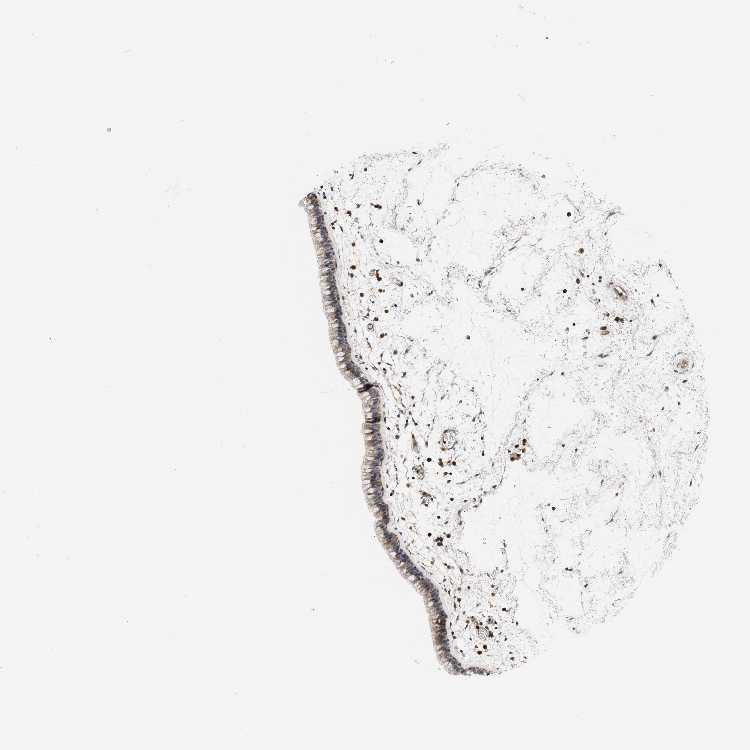

TISSUE PRIMARY DATA NASOPHARYNX Show tissue menu

Nasopharynx

NASOPHARYNX - Antibody stainingi

Antibody staining in the annotated cell types in the current human tissue is reported as not detected, low, medium, or high, based on conventional immunohistochemistry profiling in selected tissues. This score is based on the combination of the staining intensity and fraction of stained cells.

Each image is clickable and will lead to virtual microscopy that enables deeper exploration of all samples and also displays staining intensity scores, fraction scores and subcellular localization as well as patient and tissue information for each sample.

Antibody HPA020265Antibody HPA027735

Respiratory epithelial cells MediumLow